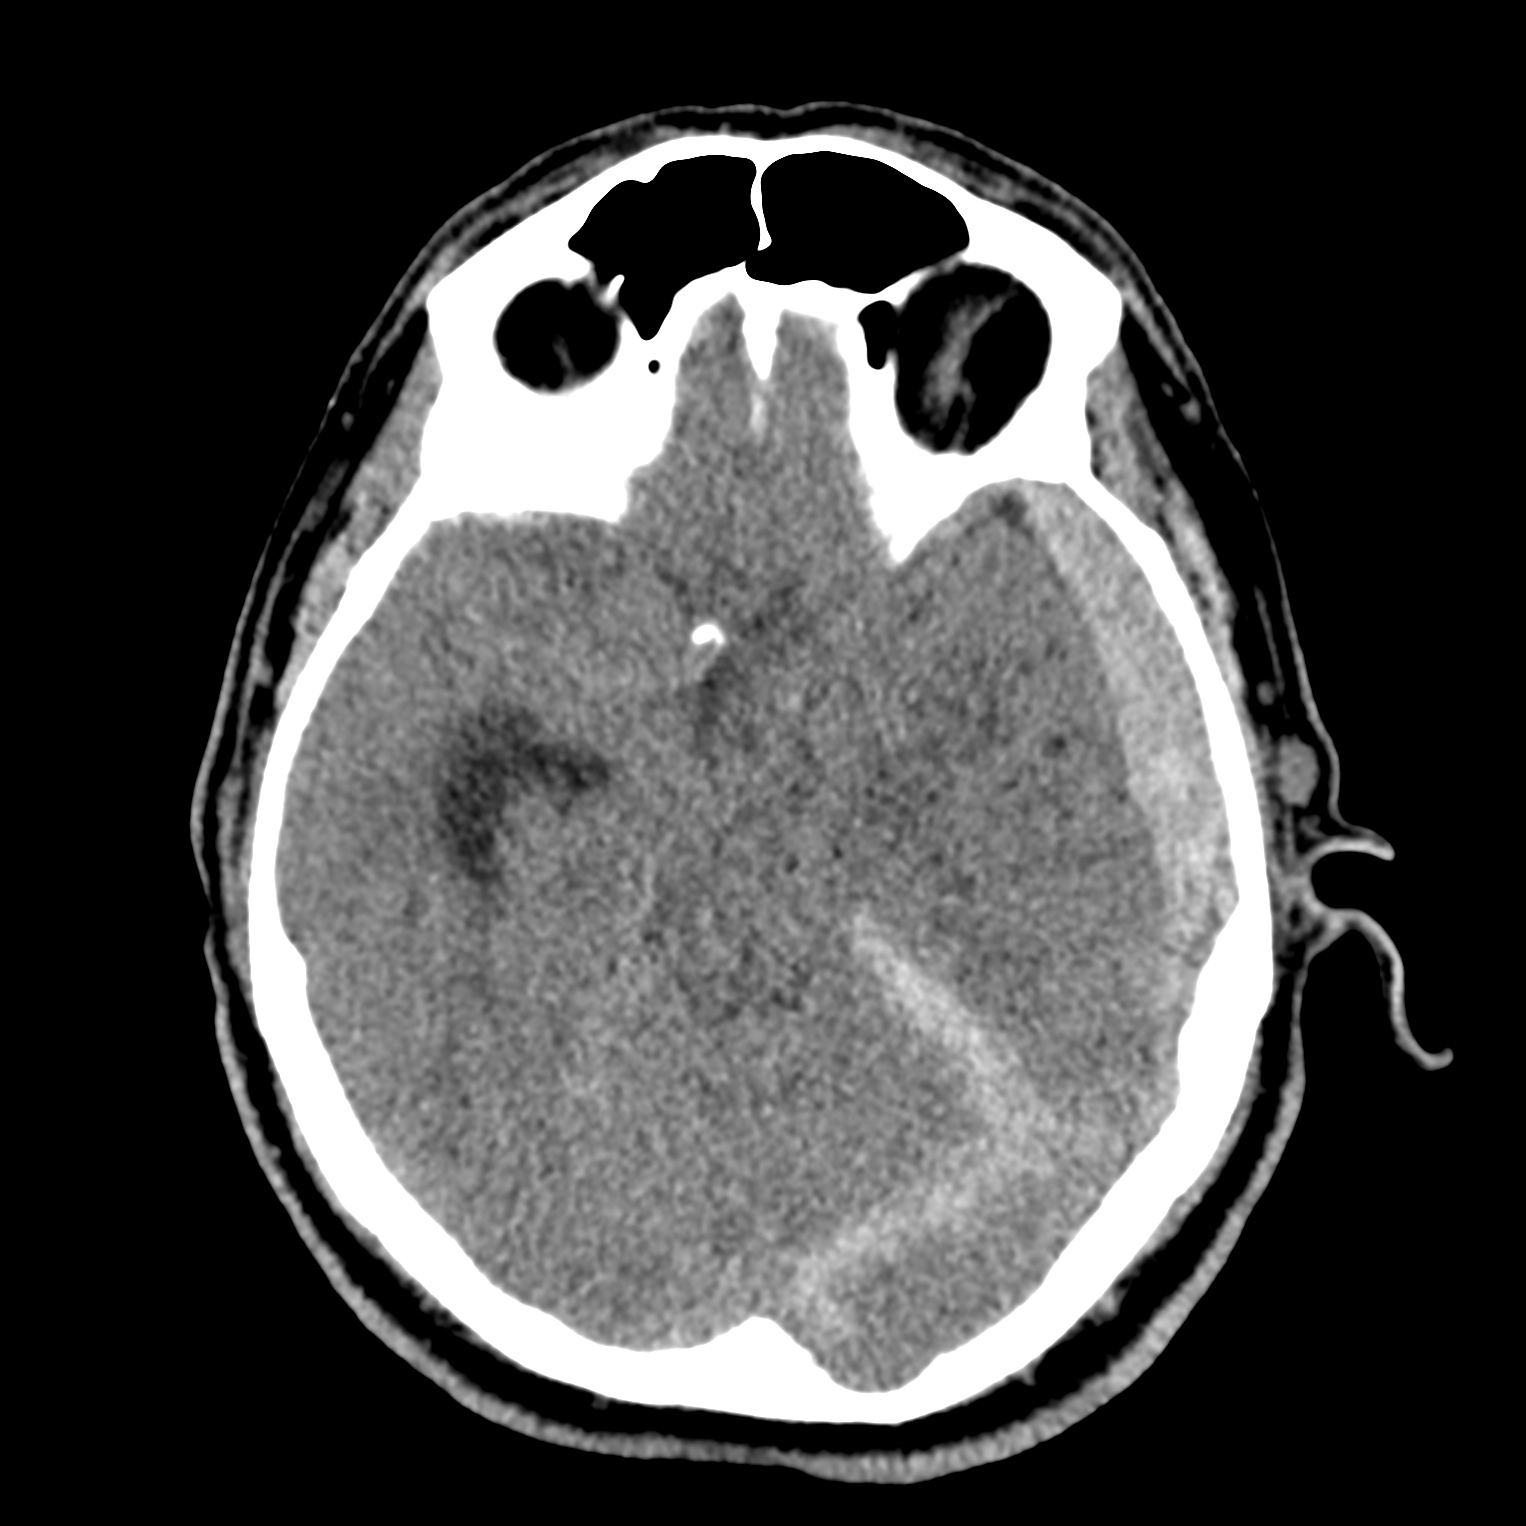

ちなみに画像診断とは、CTやMRIなどの画像を見て、正常か異常か、異常であればそれが何なのかを診断する仕事です。

Case courtesy of Andrew Dixon, Radiopaedia.org. From the case rID: 32383

医療従事者でなければ何のメリットも無いかもしれないのですが、実際の画像を自分でスクロールしながら学ぶことができるというのは、ものすごく大きなことだと思います。

さらに症例の解説を付け加えたら、読影能力アップのための強力なツールになるのではないかと期待しています。